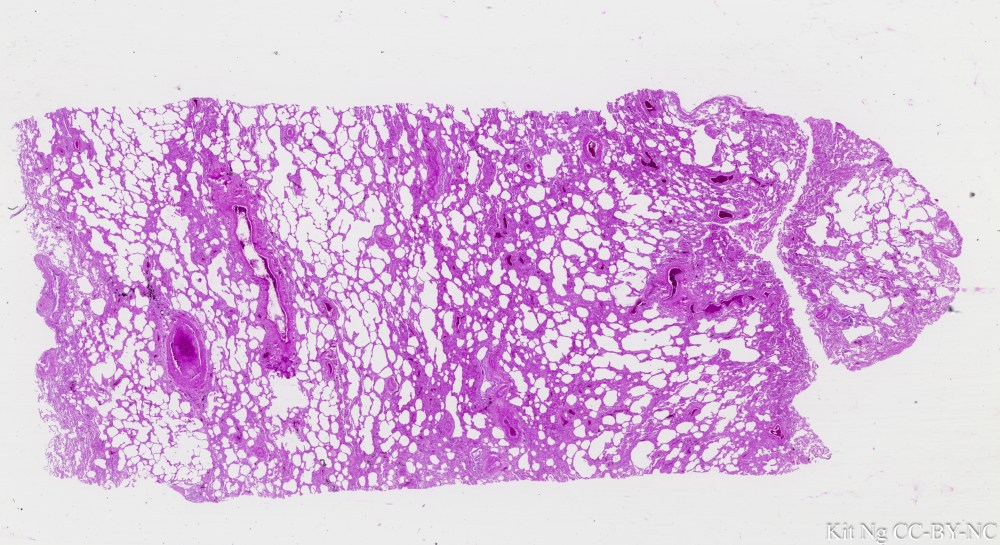

Lung human #2.jpg

Human Lung (TM: ~2.5x, picture taken with a Nikon Coolscan V slide scanner)